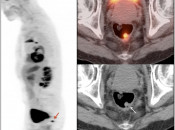

After the stomach, normal intense colon uptake is the most over-called “abnormality” by the inexperienced PET/CT radiologist.

The colon — focally or diffusely — often demonstrates intensely uptake of FDG.

Proposed mechanisms for colonic uptake of FDG include muscle contractions, the presence of lymphoid tissue and intraluminal contents.

The most common sites of normal physiologic intense colon uptake are the cecum and the distal rectum.

Generally, colonic uptake should be considered normal unless:

- There is an accompanying CT abnormality (e.g. focal bowel wall thickening or focal mass); or

- A solitary focus of intense uptake presents in an otherwise non-avid (or minimally avid) colon. Although this focal uptake may still represent normal physiologic uptake, it is reasonable to raise the possibility of a small polyp and recommend colonoscopy (polyps are rarely visible on the CT images).

We generally report, “As an adenomatous polyp or other pathology cannot be excluded, further evaluation with colonoscopy may be warranted, if not recently performed.”

Caveats:

Hemorrhoidal Inflammation:

Focal intense uptake in the ano-rectal region is a very common finding. It is considered normal in the absence of an associated soft tissue abnormality. It is often attributed to hemorrhoidal inflammation.

Be careful to not confuse ano-rectal uptake (typically representing hemorrhoidal inflammation) with rectal uptake (often malignancy).